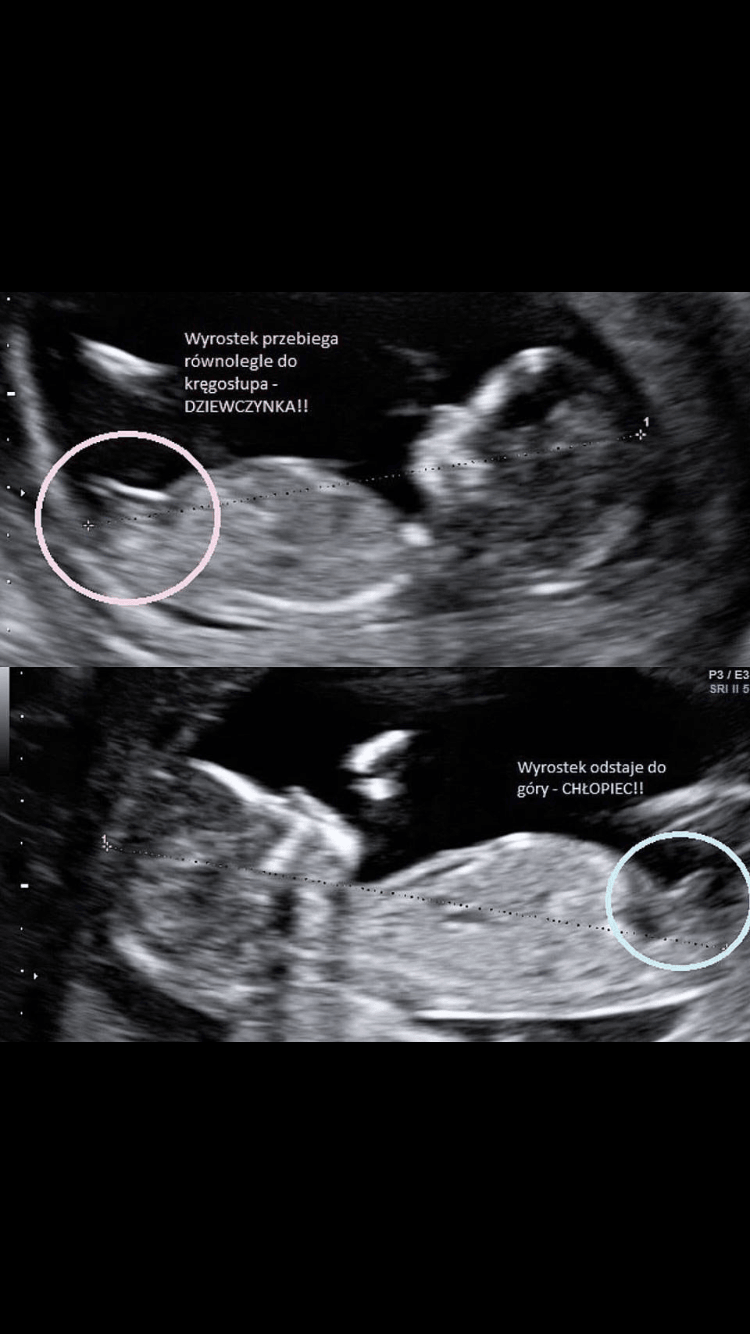

Tajniki pracy ginekologa/ultrasonografisty Jak rozpoznać płęć dziecka w I trymestrze

Aby ocenić płeć musimy uzyskać dokładny przekrój przez sam środek dziecka - jest to przekrój który jest używany do pomiaru CRL (długości ciemieniowo siedzeniowej)- czyli większość z was powinna takie zdjęcie swojego dziecka dostać- co nie znaczy że na każdym zdjęciu będzie widać to co nas interesuje bo czasami obraz nie jest jednoznaczny...

Następnie patrzymy w okolice spojenia łonowego, tam jest takie coś co roboczo nazywam "wyrostkiem płciowym" u chłopców odstaje do góry pod mniej lub bardziej ostrym kątem, u dziewczynek wyrostek ten jest też dość gruby i widoczny ale przebieg równolegle do kręgosłupa. zdjęcie pokazujące wam na co patrzeć